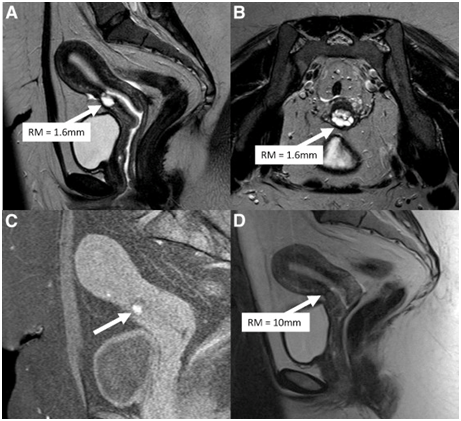

Figure 2 Courtesy ref 6-(A) Preoperative sagittal view of a T2-weighted image shows the residual myometrium (RM; white arrow) measuring 1.6 mm, covering a deep cesarean scar defect. (B) Preoperative transversal view of a T2-weighted image from the same patient. The RM covering the scar (white arrow) is very thin. (C) Sagittal view of a T1-weighted image with saturation of fatty tissue showing hypersignals (white arrow) inside the cesarean scar defect, suggestive of blood retention. (D) Sagittal view of a T2-weighted image after laparoscopic repair. The defect is no longer visible, and the RM at the level of the isthmus (white arrow) measures 10 mm.